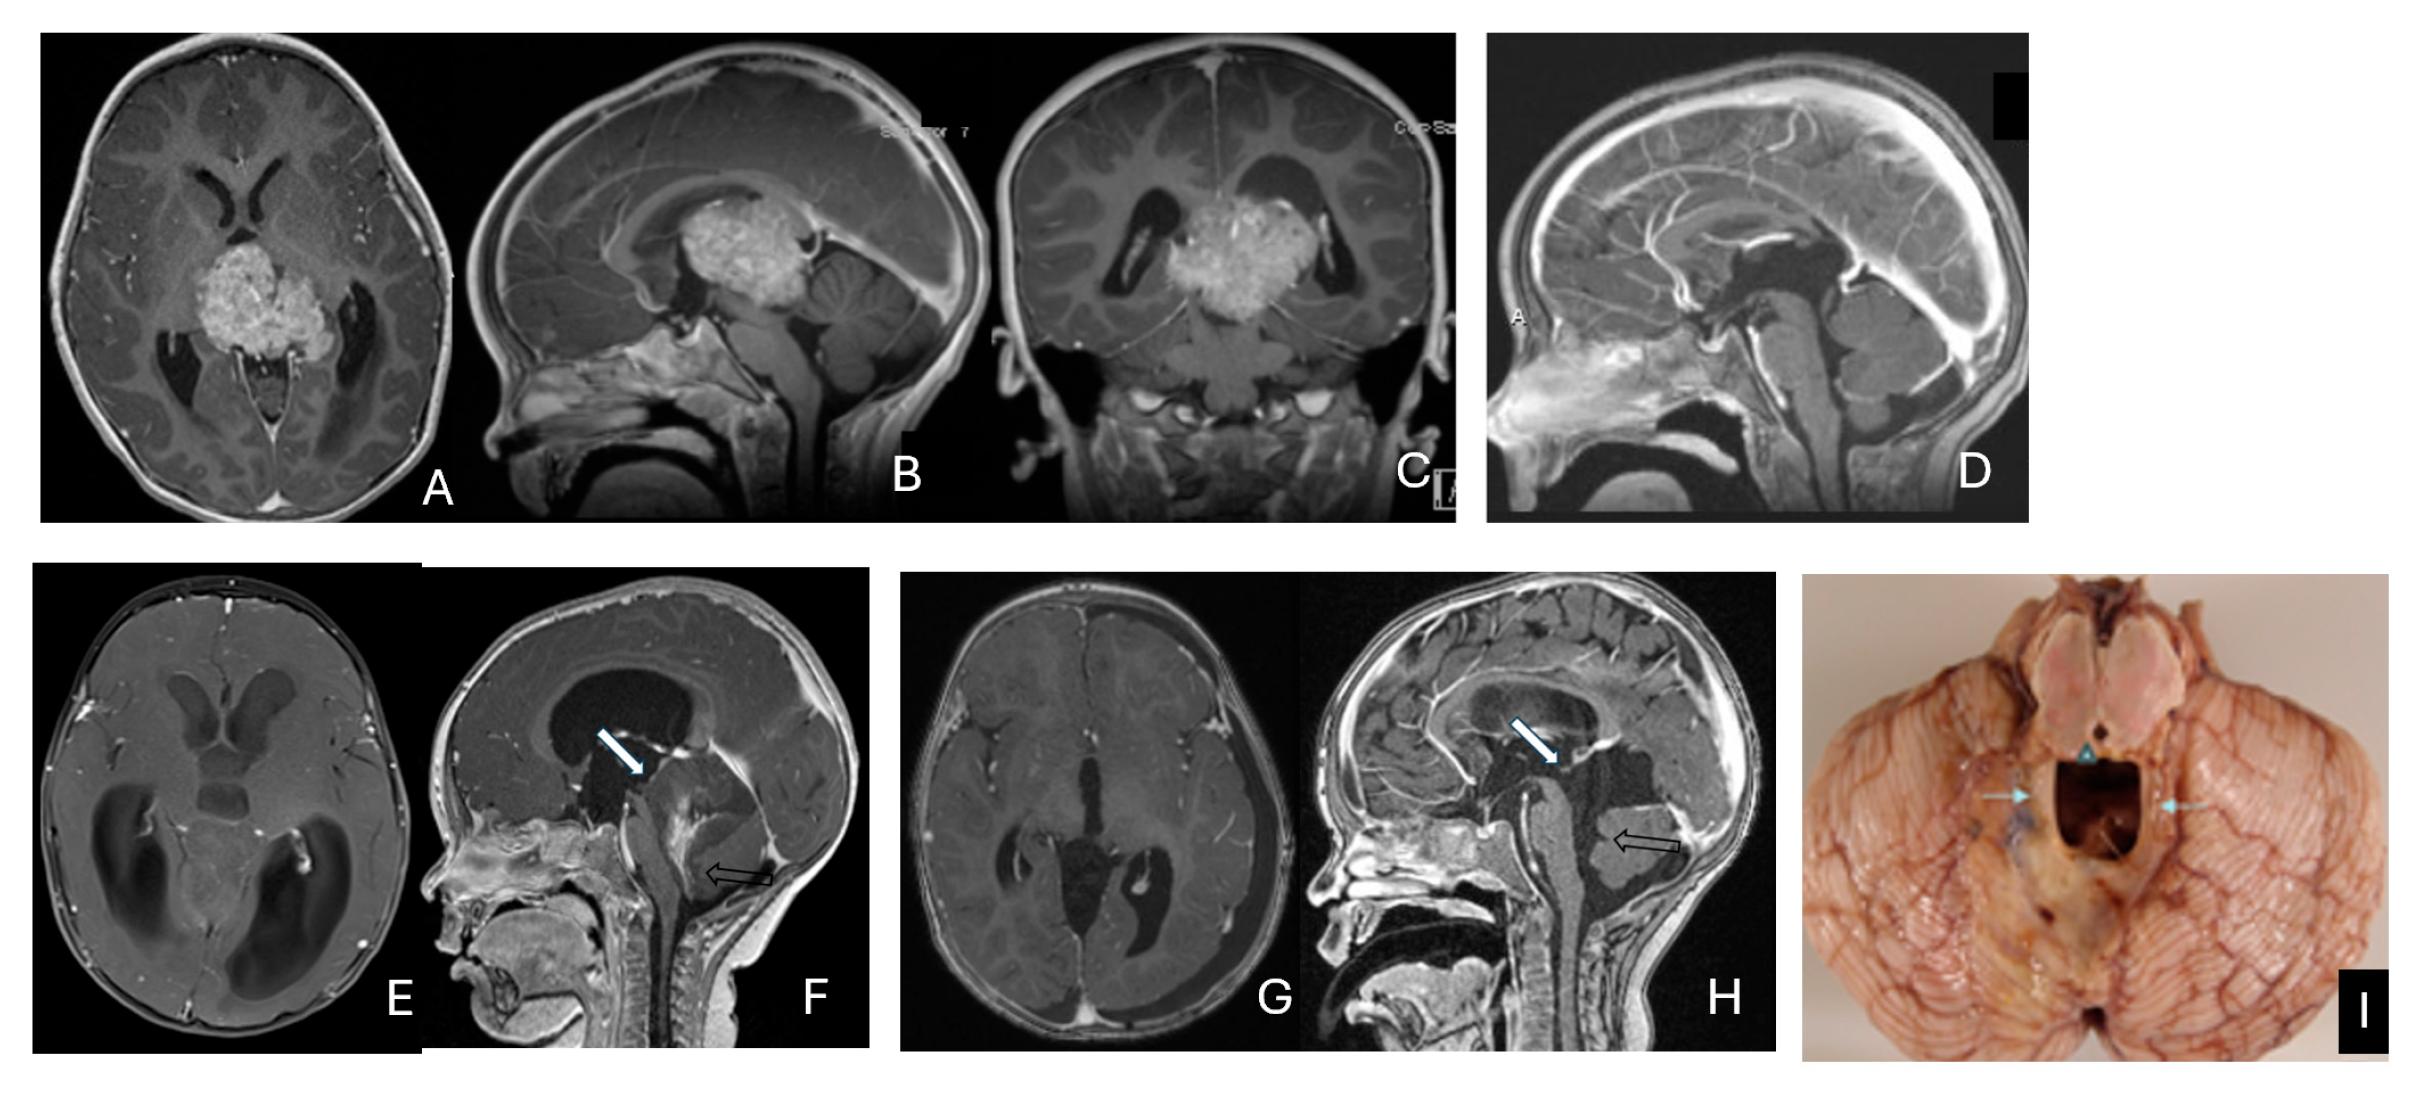

3.4. Spine AT/RT

Among the six patients diagnosed with ATRT of the spine, ages ranged from 7 months to 134 months, with a median age of 85 months. Notably, the median age at diagnosis was 80 months, which is older than that of patients with intracranial ATRT.

Only one case involved an intramedullary tumor located in the cervical cord of a 34-month-old girl (Figure 11A–D). Two patients, a 64-month-old girl and a 96-month-old girl, had intradural extramedullary tumors situated at the T12-L1 and L3-S2 levels, respectively. Additionally, a 7-month-old girl presented with a contiguous intradural extramedullary and extradural tumor that extended outward to the paraspinal structures (Figure 11E–I). She underwent a staged operation, initially through a cervical laminoplastic laminotomy at the C5–7 level, followed by a second surgery via an anterior cervical approach for the total resection of the extraspinal disease after chemotherapy.

Figure 11.

Spine ATRT. (A–D): MR images ((A), sagittal; (B), axial) of a 34-month-old girl show a heterogeneous intramedullary cervical tumor centered at C3–C5. Postoperative images ((C), sagittal; (D), axial) demonstrate gross-total resection. (E–I): T2-weighted sagittal MR (E) and post-contrast axial MR (F) of a 7-month-old girl show a C5–C7 intradural–extramedullary ATRT with extradural and extraspinal extension (open arrow). The intradural–extramedullary component from the C6 dorsal nerve root and the epidural component into the neural foramina were resected (G), sagittal; (H), axial through a laminoplastic laminotomy, note a persistent paraspinal tumor (open arrow). Following chemotherapy, the residual paraspinal component was subsequently resected via an anterior cervical approach ((I), axial). (J–M): Mid-thoracic MR images ((J), sagittal; (K), axial) of a 9-year-old boy show a dorsal epidural ATRT from T7 to T9 with right-sided neural foraminal extension (arrow). An epidural ATRT was removed through laminectomy ((L), sagittal; (M), axial).

Another child, the oldest in this cohort, was an 11-year-old boy who presented with a dumbbell-shaped intradural extramedullary ATRT extending into the extradural space and neural foramina at the C5-T11 levels. Additionally, a 9-year-old boy had ATRT located in the epidural space, extending into the neural foramina at the T7–9 levels (Figure 11J–M).

The cerebellar peduncular, vermis, and CPA/CMF are common site of ATRTs. Most ATRT-TYR tumors arise from the middle cerebellar peduncle and inferior vermis [76] and can extend exophytically into the cerebellopontine angle (CPA) and cerebellomedullary fissure (CMF). ATRT-MYC tumors can originate from cranial nerves in the CPA, producing imaging appearances that overlap with TYR tumors; however, the age distribution differs, with TYR typically affecting much younger children than MYC. Infratentorial ATRTs frequently mimic posterior fossa ependymomas in their location and propensity to extend into the CPA and fourth ventricle, but ATRTs tend to be more infiltrative, whereas ependymomas are usually expansile and less invasive [77]. Consistent with this pattern, the European Rhabdoid Registry reports cranial nerve involvement occurs in approximately 3% of ATRT cases and is most often associated with the MYC subgroup [62]. One female patient with CPA ATRT of CPA, who was notably the oldest in this cohort, had a tumor that likely originated from the vestibular nerve, without involvement of the brainstem or cerebellum. (Figure 12).

Figure 12.

CPA ATRT. (A–D): MR images ((A): axial; (B): coronal) of a 20-year-old girl, the oldest in this cohort, who presented with left-sided hearing loss and partial facial weakness, reveal ATRT that appears to originate from the vestibular nerve. Surgical findings and post-resection MR images ((C): axial; (D): coronal) indicate no tumor invasion into the cerebellum or brainstem, which contrasts with typical presentations of infantile ATRT.